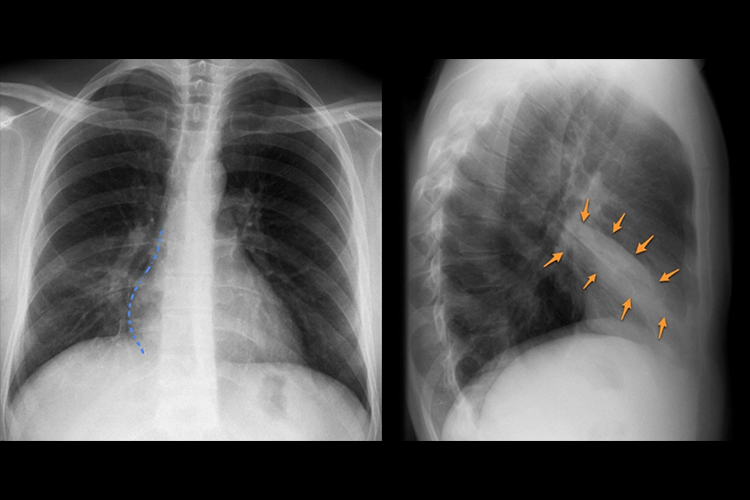

肺内片状模糊影

正常肺组织主要为含气的肺泡,若有积液、渗出、增生、机化或瘤细胞浸润时,胸片上可呈片状模糊影,表现有密度比肋骨低,小片状分布;密度与肋骨相似或略高,病变边缘模糊不清;病灶呈梭形、边缘锐利等。

常见于肺部炎症、肺内出血或渗血、肺脓肿、包裹性胸腔积液、肺叶间积液等疾病。